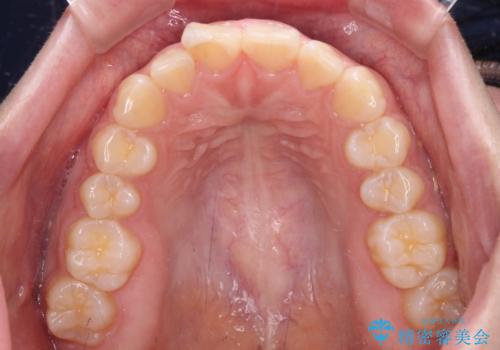

- 出っ歯と口の閉じにくさ、デコボコを気にして来院された患者様です。

口元の突出感を改善するため、上下左右第一小臼歯4本の抜歯を行い、ワイヤー装置による矯正治療を行うこととしました。

抜歯矯正を行ったことで、顎先のつっぱり感や口元の閉じにくさを解消することができました。